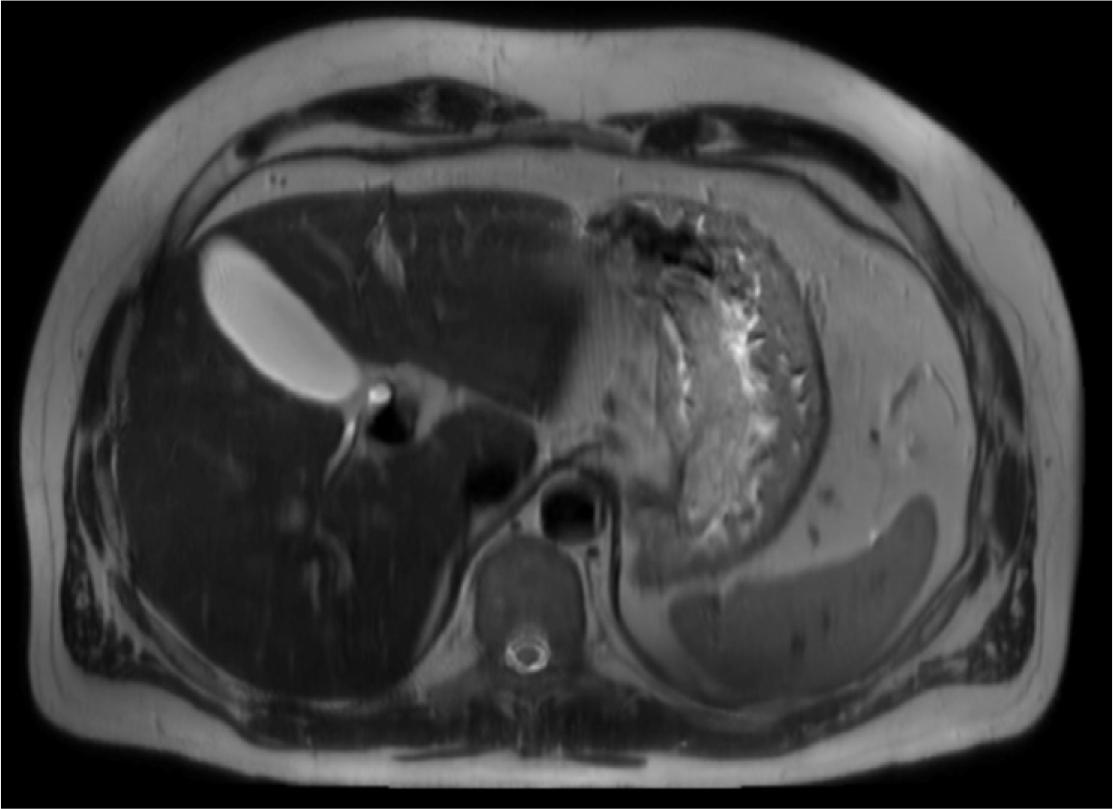

MRI, T2-weighted, axial view – Abdominal cross-sectional T2-weighted MR image demonstrates a large, thickened, edematous gastric wall along the lesser curvature, with preserved rugal folds. This image is atypical for gastric cancer and raises differential diagnoses such as lymphoma, hypertrophic gastritis, or Zollinger-Ellison syndrome.

In August 2024, an abdominal MRI with MRCP was performed for further assessment. Two separate abnormalities were revealed. The first was a 106 × 34 mm abnormal widespread mass of thickened, edematous wall along the lesser curvature near the cardiac orifice of the stomach, with retained rugal folds. However, this image was not representative of typical gastric cancer infiltration. This image was nonspecific and required histopathological verification. Differential diagnoses included gastric lymphoma, hypertrophic gastritis, and Zollinger-Ellison syndrome.